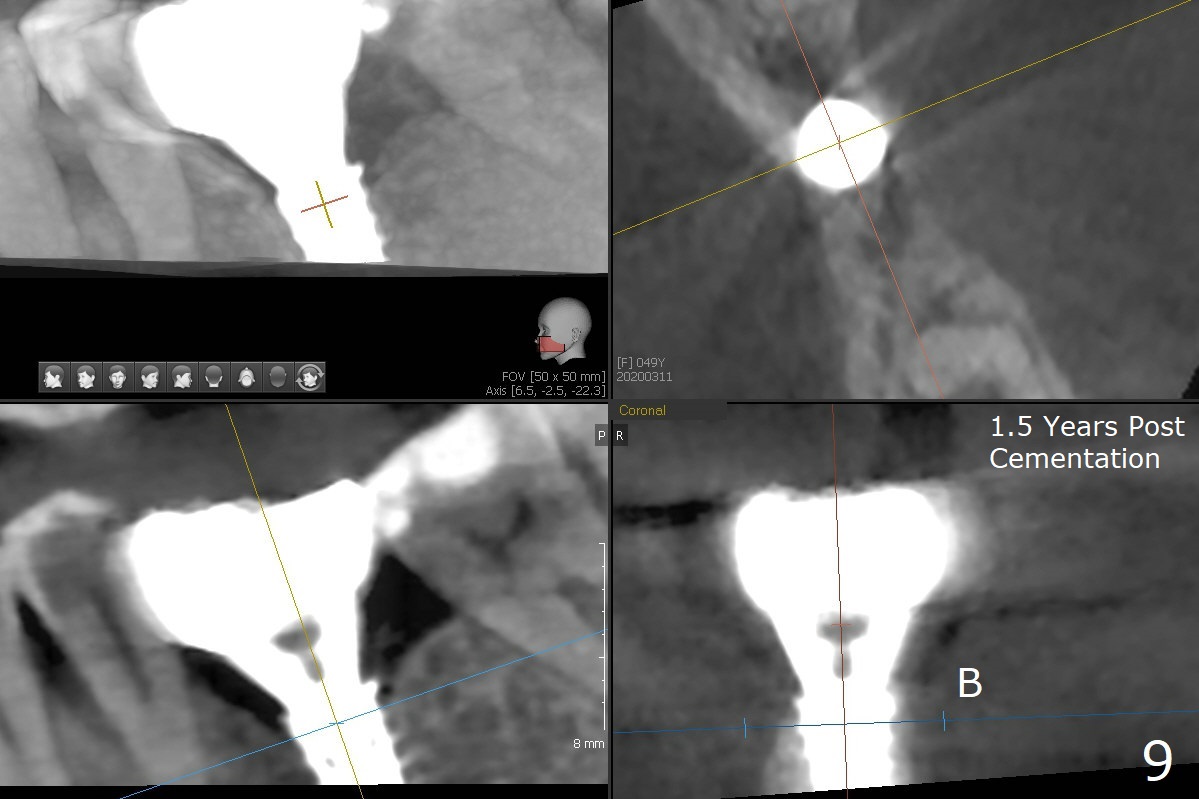

While the mesial ridge is relatively wide associated with residual root at #19 (Fig.1 <), the distal one is narrow (*). Osteotomy is initiated distal to the mesial socket (Fig.2,3 *). Due to the narrow ridge, a 4.5x11 mm implant is placed (Fig.4); before as well as after placement of a 6x4(3) mm abutment, the mesial socket (*) is filled with Vera graft and autogenous bone as well as collagen plug. Following suturing, periodontal dressing is applied to the wound. There is no apparent bone loss 7 months postop (Fig.5,6) or 14 months post cementation (Fig.7). In fact the abutment has been incompletely seated (Fig.5-8), which may be related to #13 failure. The ridge appears to be narrow for the 4.5 mm implant 1.5 years post cementation (Fig.9). When a lady looks skinny with sign of the narrow ridge, choose an implant as narrow as possible.